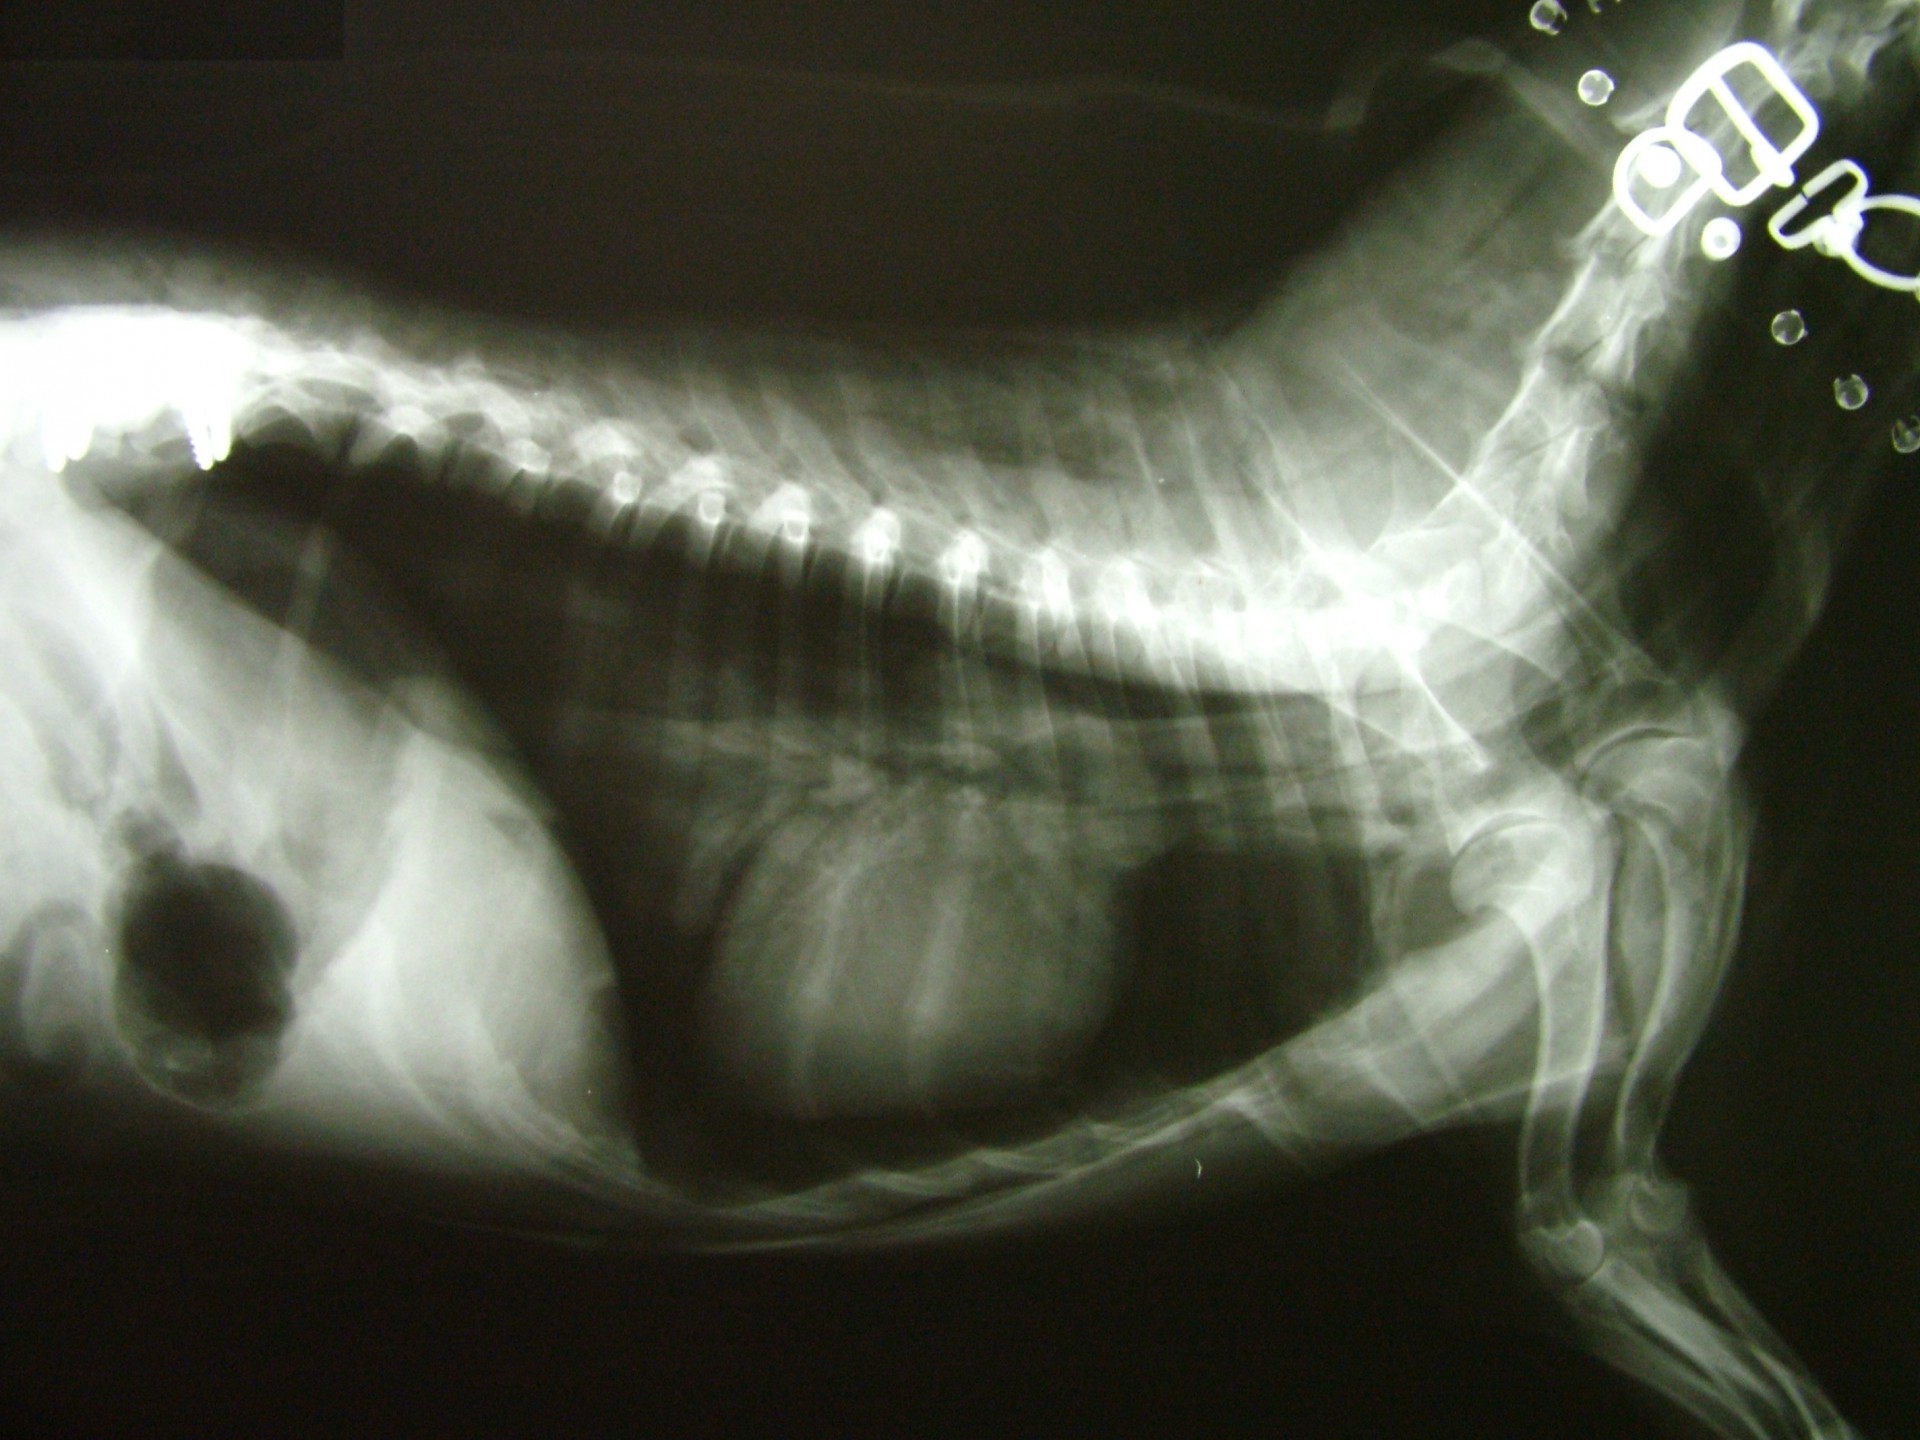

A gerinctörések kialakulását minden esetben valamilyen súlyos trauma előzi meg. Az esetek döntő részében a tulajdonos a kórelőzményben ezt elmondja, de nem egy esetben találkoztunk talált, ismeretlen kórelőzményű, súlyos neurológiai tüneteket mutató állattal.A trauma általában kutyák esetében gázolás, kistestű kutyák (yorkshire terrier, chihuahua) esetében nagytestű kutya harapása, macskák esetében kutyaharapás, gázolás vagy emeletről történő leesés.

A gerinctörött állatok általában súlyos fokú hátsó testfél gyengeség tüneteit mutatják, a sérülés helyétől függően (a gerincoszlop mely szakaszán alakult ki gerincvelő sérülés) azonban a tünetek a mellső végtagokat is érinthetik. Ilyen tünetegyüttes a Schiff-Sherrington syndroma, melyben a gerincvelő sérülése mögötti területen petyhüdt bénulás, míg a sérülés előtti területen a nyújtó izmok fokozott tónusának megjelenése jellemző.

A gerincsérült állatokat ért traumás behatás természetesen nemcsak a gerincoszlopot, hanem egyéb szerveket is érhetik, ezért a gerincvelő sérülés ellátásához rendelkezésünkre álló idő (általában 24 óra) sok esetben az egyéb szervi sérülések miatt meglehetősen rövid vagy az egyéb sérülések következményei - egy akár sikeres gerincműtétet követően is - az állat halálát okozhatják. Ezért a balesetes állatok sérüléseinek ellátása fontossági sorrendben kell hogy megtörténjen, hisz eredményt csak akkor érhetünk el, ha az állat állapotát stabilizáljuk.

A gerinctörés diagnózisának felállítása komoly döntés elé állítja a tulajdonost és az állatorvost egyaránt. A gerinctörés következtében a gerincvelő minden esetben enyhébb-súlyosabb mértékben sérül. A gerincvelő sérülésének mértékét neurológiai vizsgálattal állapítjuk meg, de a diagnózis felállításához nélkülözhetetlen röntgen felvételről is már információt nyerhetünk a gerincvelő várható állapotáról. A tört végek egymáshoz képest történő kis mértékű elmozdulása esetén a gerincvelő körüli területek bevérzése miatt kialakult neurológiai tünetekkel találkozunk míg nagymértékű elmozdulásuk a gerincvelőt gyakorlatilag olló szerűen elnyírhatja. Így a natív röntgen felvételen a gerinccsatorna elmozdulásából már következtetést vonhatunk le a gerincvelőt ért sérülés mértékéről. A gerincvelő tényleges állapotáról azonban csak neurológiai vizsgálattal győződhetünk meg!